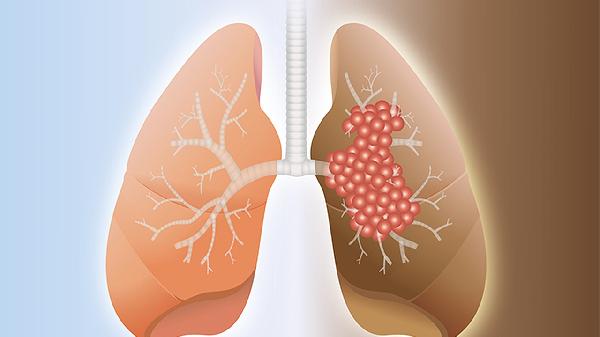

肺炎胸片多显示斑片状浸润影,磨玻璃样改变多见于病毒性肺炎。肺癌CT可见分叶状肿块伴毛刺,支气管截断征较具特异性,增强扫描显示不均匀强化。PET-CT中肺癌标准摄取值通常显著高于肺炎病灶。